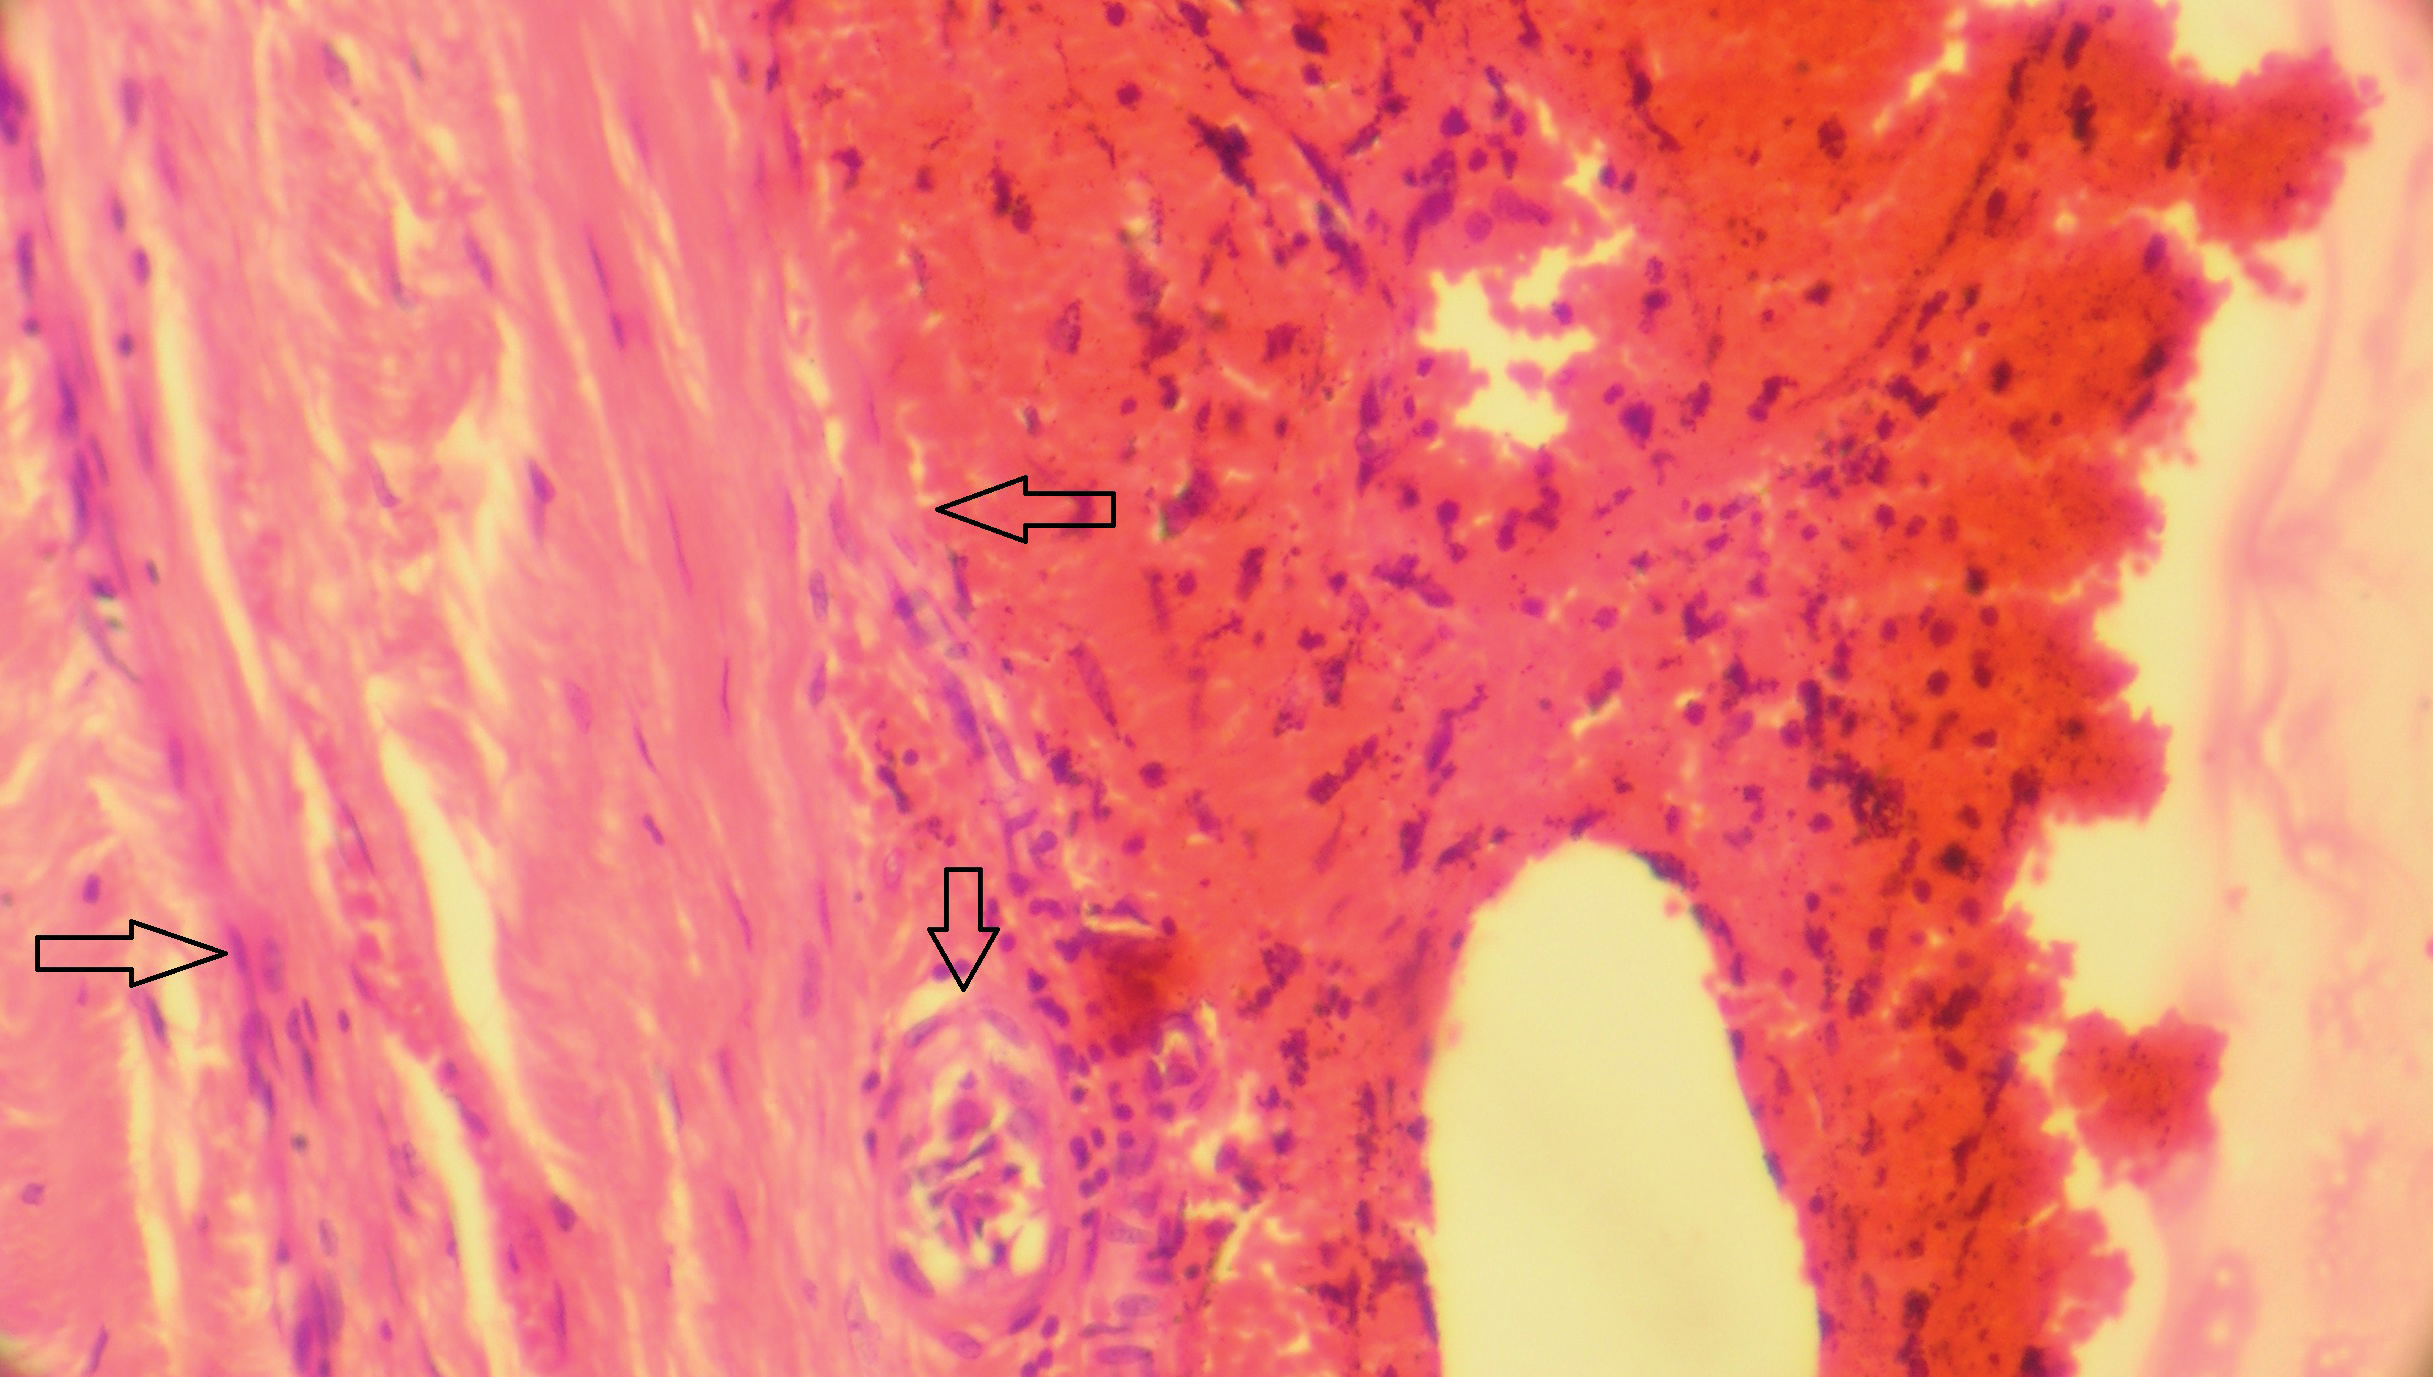

Важным элементом новой классификации является выделение в ней трех подгрупп среди инкапсулированных СГ. Основную долю СГ данного типа представляют гематомы давностью более 3 суток, подвергшиеся инкапсуляции в ходе своей естественной эволюции. Однако кроме них формально к данному типу относятся также каузально не связанные с первичными повторные субдуральные кровоизлияния, в том числе острые, локализация которых в субдуральном пространстве полностью или частично совпадает с локализацией очагового субдурального фиброза в исходе перенесенной первичной СГ. В отличие от первично инкапсулированных СГ данный тип гематом целесообразно именовать вторично инкапсулированными (рисунок 4).

Рисунок 4. Вторично инкапсулированная СГ. Состоит из остатков капсулы организованной первичной СГ, имеющей строение, схожее с таковым ТМО (границы капсулы отмечены горизонтальными стрелками) и наложений крови повторной острой СГ. В капсуле виден сосуд метакапиллярного типа (отмечен вертикальной стрелкой). Окраска гематоксилином и эозином. 129х.